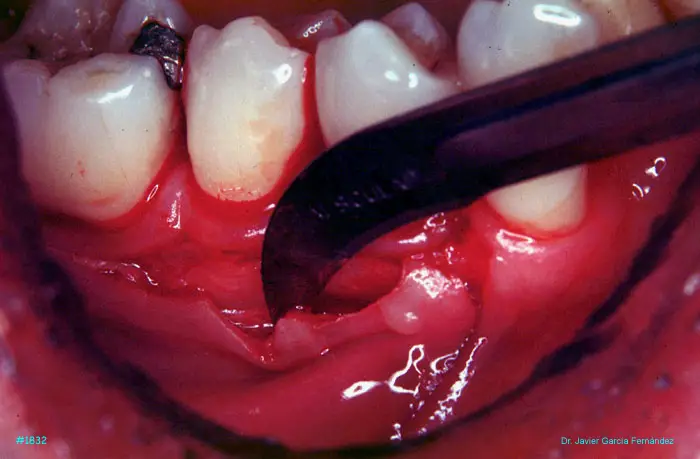

image 98